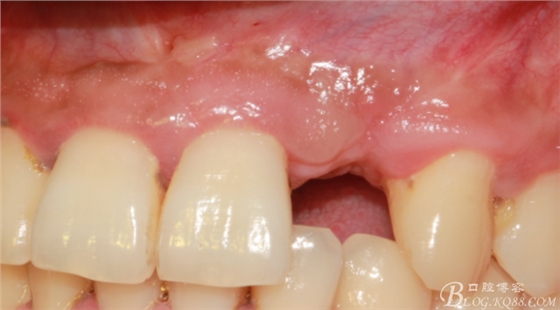

4個(gè)月后,唇側(cè)豐滿度尚可,與鄰牙之間齦乳頭完整。

保留齦乳頭翻小瓣。